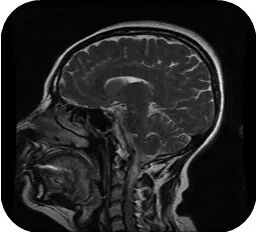

颅脑MRI:双侧额叶脑白质内脱髓鞘改变;双侧上颌窦炎;右侧乳突炎。